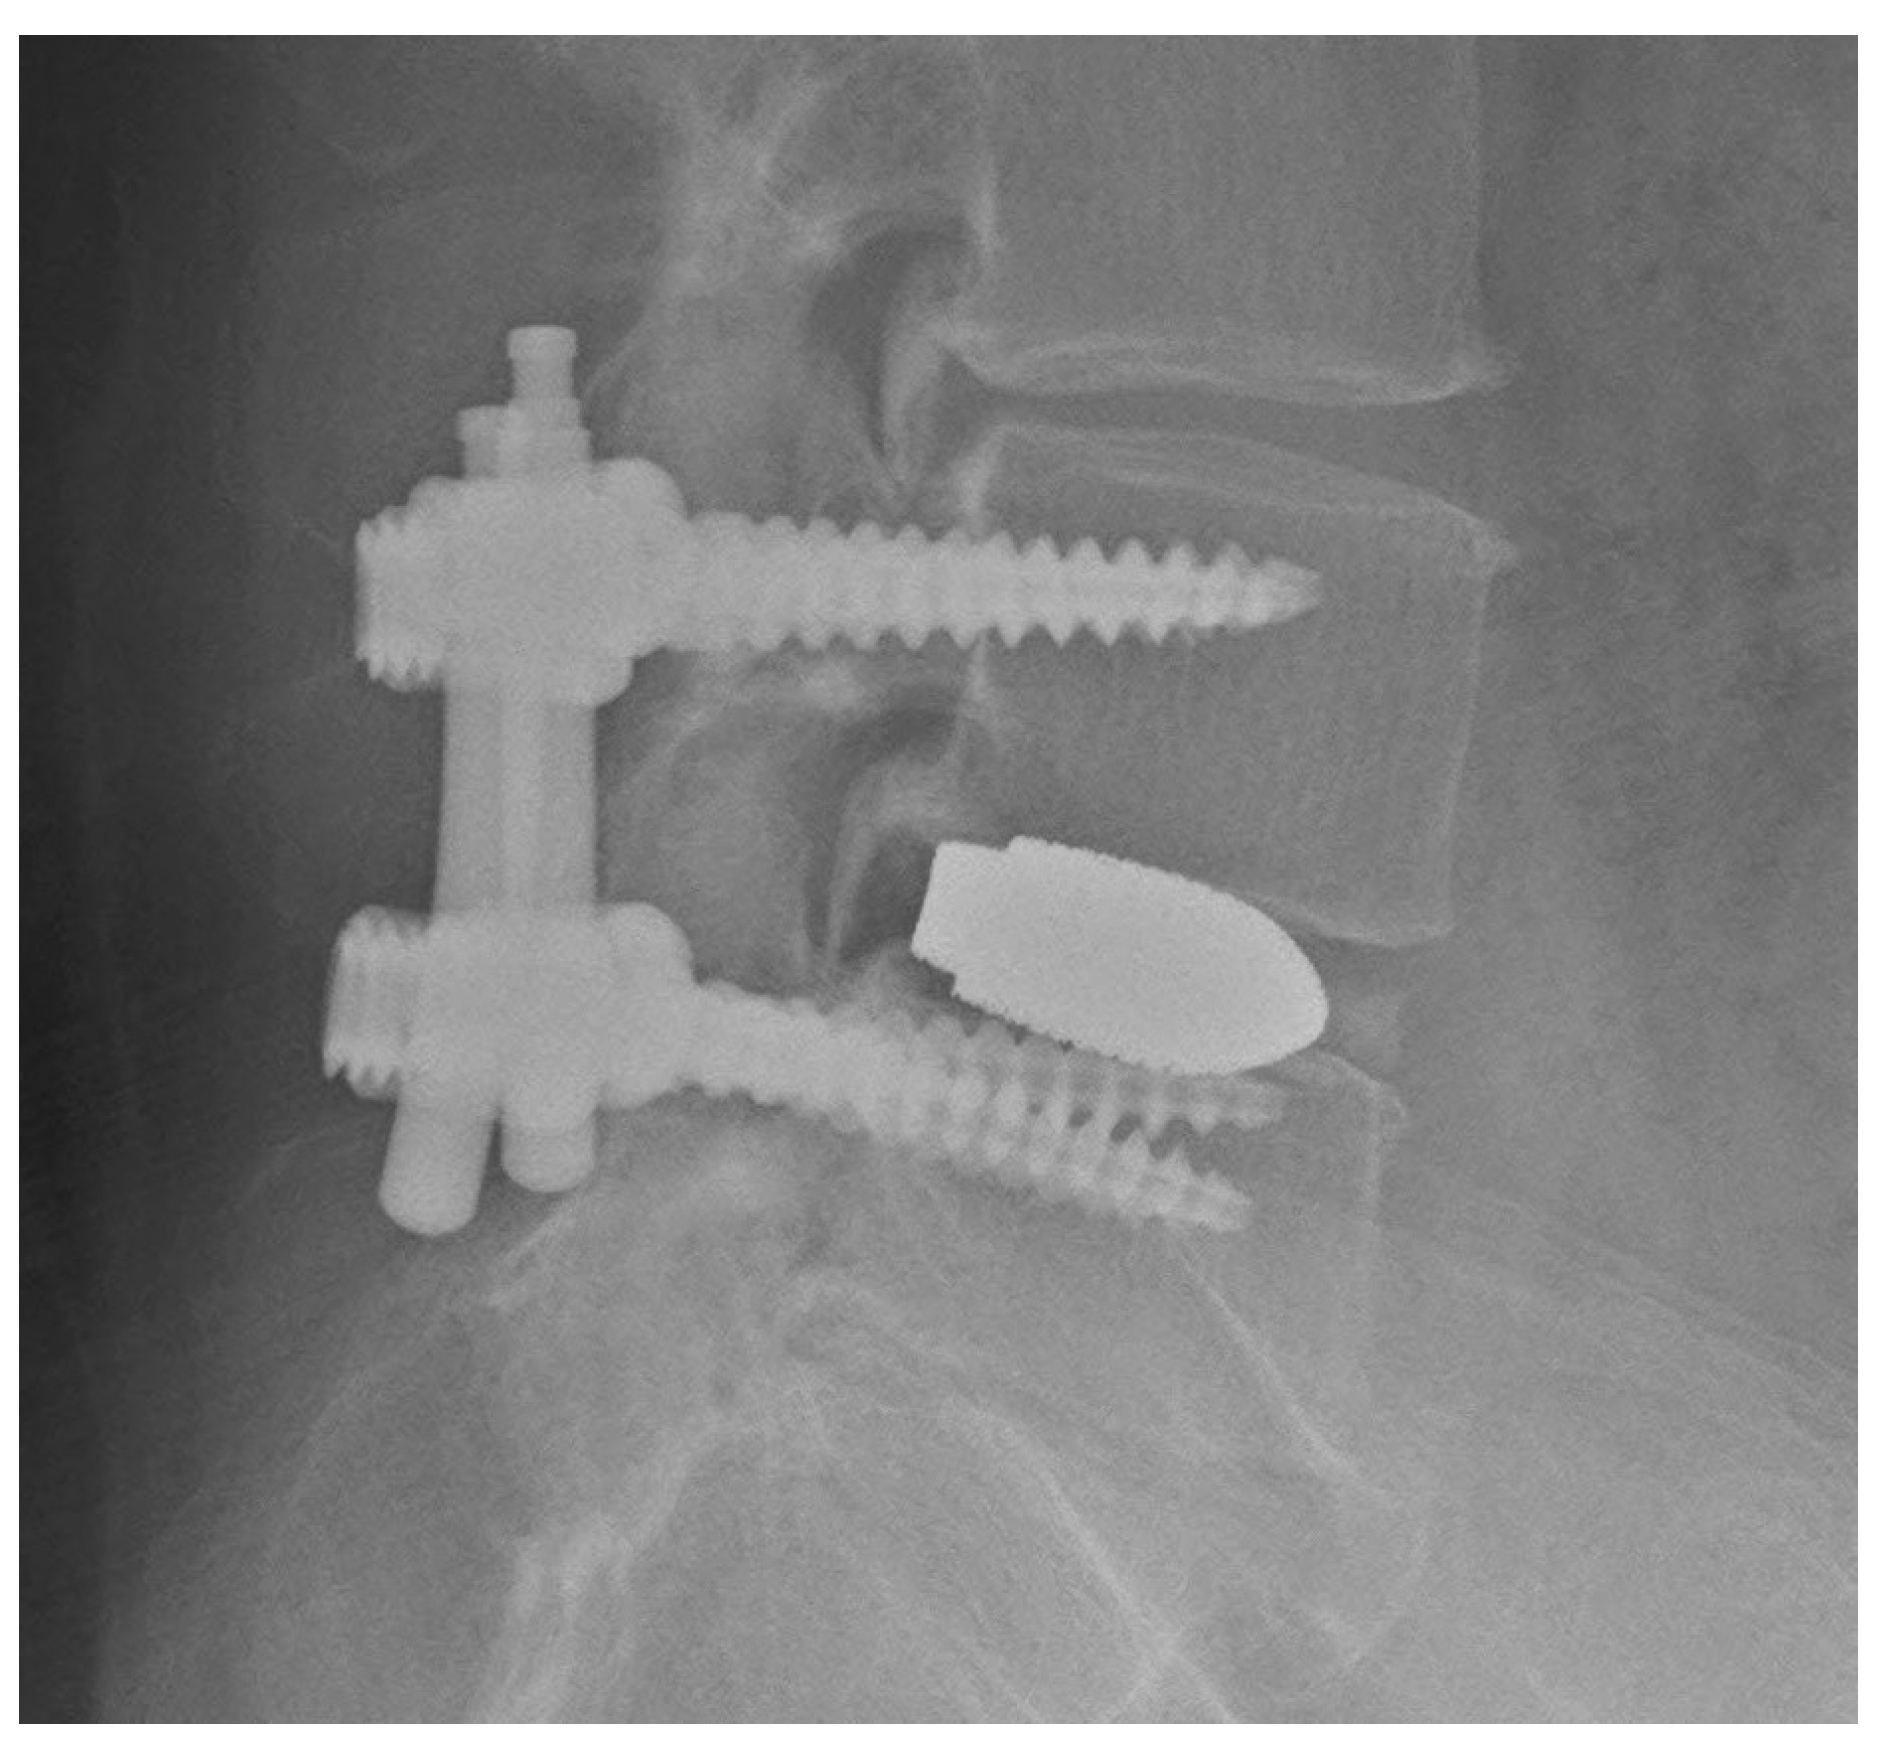

3.4. Adverse Events

In one patient with a grade D breach (Figure 7a,b), screw deviation of the medial pedicle wall with numbness of the right foot developed postoperatively. After reoperation, the symptoms resolved, and no residual neuropathy was observed in this patient. The extra time required for this new procedure was also considered. The extra time was defined from the start of surgery to the completion of intraoperative radiography of the pedicle marker. The average time was 39 min (range: 16–69 min; Table 2) per patient, and patient characteristics had no effect on this result (Table 3).

Figure 7.

(a,b) Computed tomography scan of the screw deviation to the medial pedicle wall in grade D breach.